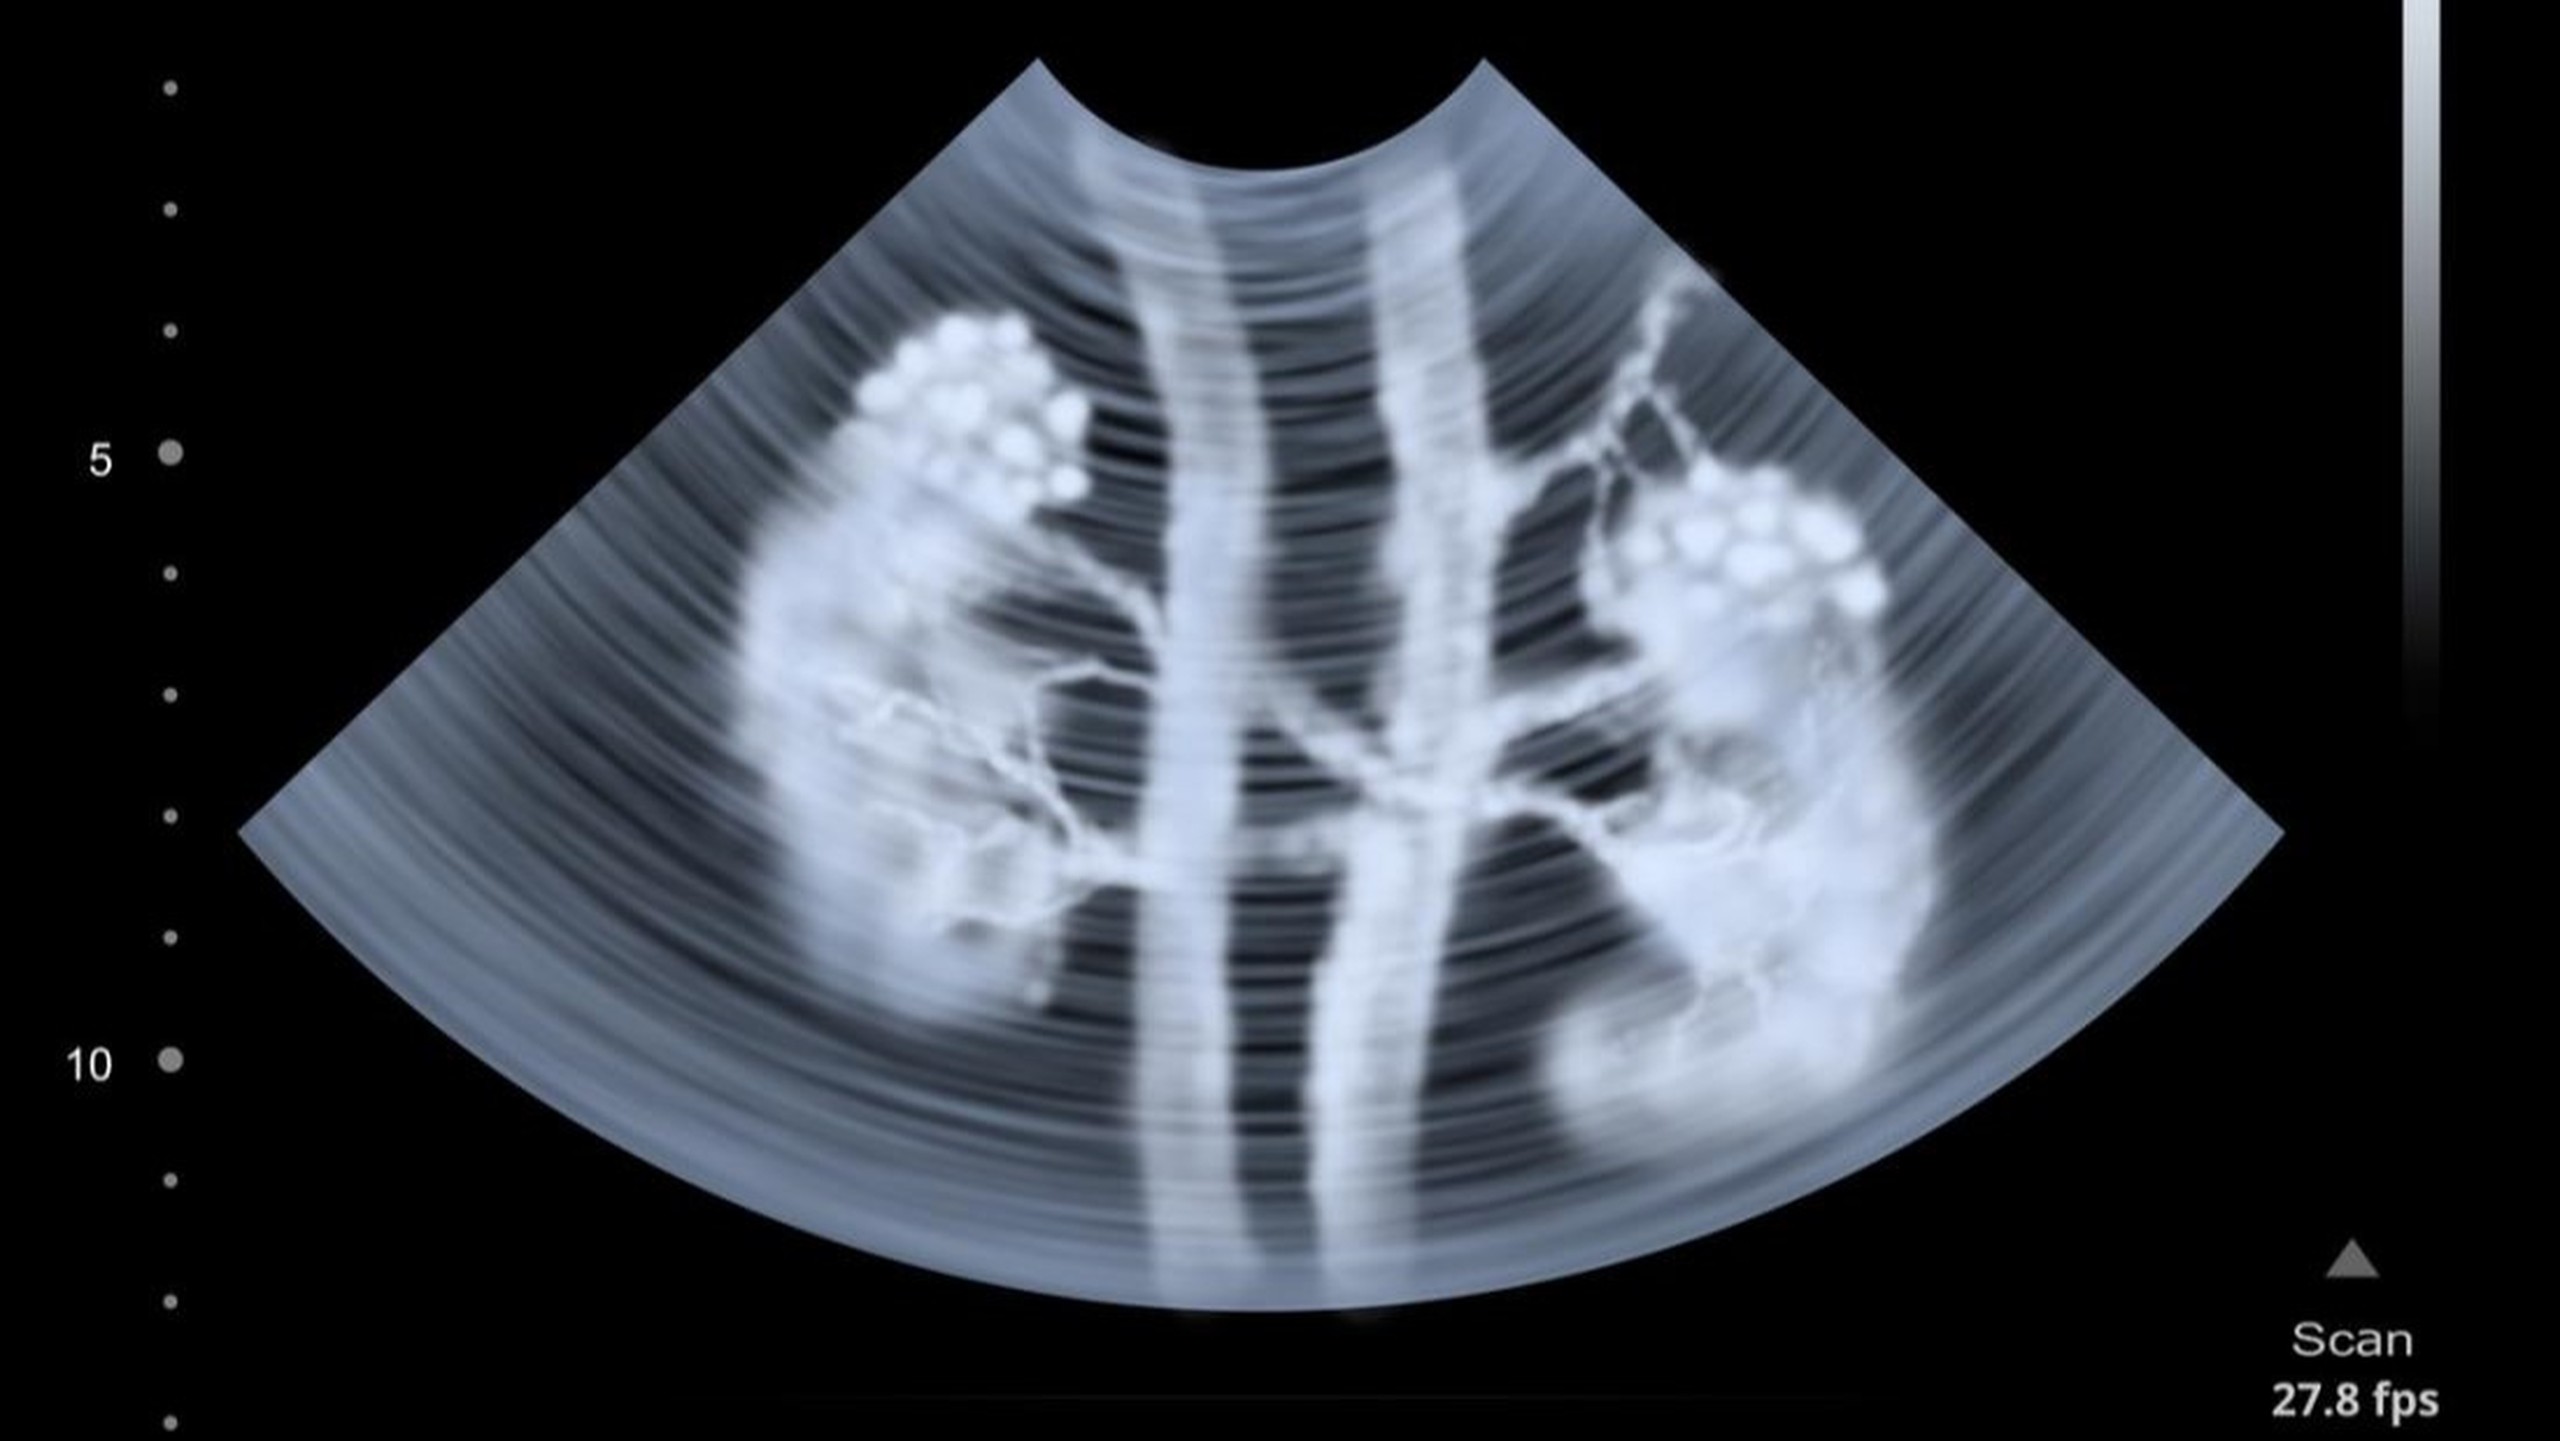

Nang đơn thận là một loại nang có thành mỏng chứa dịch hình thành ở trên bề mặt hoặc bên trong thận, đây là loại nang thận khá phổ biến. Một hoặc nhiều nang đơn lẻ có thể hình thành trong cùng một quả thận. Nang thường có dạng hình tròn hoặc bầu dục, kích thước từ hạt đậu đến quả bóng chơi golf và chúng có thể phát triển lớn dần theo thời gian.

Nang đơn thận thường được phát hiện tình cờ trong quá trình kiểm tra sức khỏe định kỳ hoặc khi thực hiện các xét nghiệm hình ảnh như siêu âm, CT hoặc MRI. Siêu âm ổ bụng là phương pháp đầu tiên giúp xác định kích thước và vị trí của nang. Nếu cần thêm thông tin, chụp CT hoặc MRI có thể được sử dụng để đánh giá chi tiết hơn về nang. Trong trường hợp nang không gây triệu chứng hoặc biến chứng, chỉ cần theo dõi định kỳ, nhưng nếu nang lớn hoặc gây đau, bác sĩ có thể chỉ định điều trị.